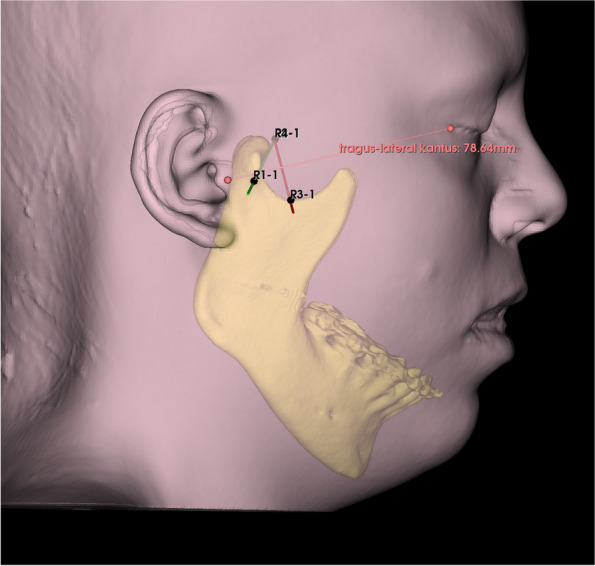

Background: This study aimed to investigate the range of angles and depths necessary for effective entry into the TMJ using CBCT images, focusing on classical Holmlund Hellsing points and a two-needle approach.

Methods: A retrospective cohort of CBCT images from January 2020 to November 2023 was analysed using 3D analysis to determine the variance in the required angles and depths.

Results: The average age of the 68 participants included in the study was 29.5 ± 11.1, 58.8% of the participants were female and 41.2% were male. The anterior needle measurements showed a relatively low standard deviation(SD) in depth(SD:3.6) with a low variance coefficient(12.5%), whereas the axial and coronal angles exhibited greater variability(SD:9.1 and 7.6, respectively). For the posterior needles, moderate SDs in depth(SD:3.5) and greater variabilities in axial and coronal angles(SD:9.6 and 5.3, respectively) were observed. A weak negative correlation was observed between the axial angle of the posterior needle and age(p: 0.028, Pearson r: -0.29) Anterior needle depth (p:0.037) and posterior needle axial angle(p:0.014) were greater in males than females. The anterior needle depth in patients with temporamandibular disease was greater than in those without(p:0,03).

Conclusion: There were significant differences in the angle measurements for both anterior and posterior needles, but lower variance in depth. The depths and angles of the needles did not correlate with age.